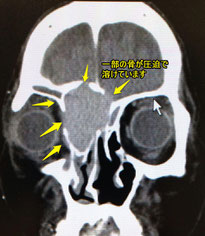

副鼻腔炎の場合、多くは蝶形洞(ちょうけいどう)や篩骨洞(しこつどう)という、眼の間や眼の奥の空洞に炎症があります。炎症そのものの痛みではなく、時には嚢腫(のうしゅ)という袋ができ、それによる圧迫で痛みが起こっている場合もあります。

特に蝶形洞に病変があると、頭の芯の痛みや、目の奥に痛みが出ることもあります。時には視力や見える範囲が狭まって来たり、二重に物が見えるといった症状が出ることもあります。

われるような目の辺りの痛みで眠れないとの訴えで来院された、子供さんです。

CTで蝶形骨洞に陰影があり、服鼻腔炎による痛みも考えられ、抗生剤の点滴を受けられました。

約2ヶ月程度、内服での副鼻腔炎の治療を行い、蝶形骨洞炎が消えたのを確認しました。